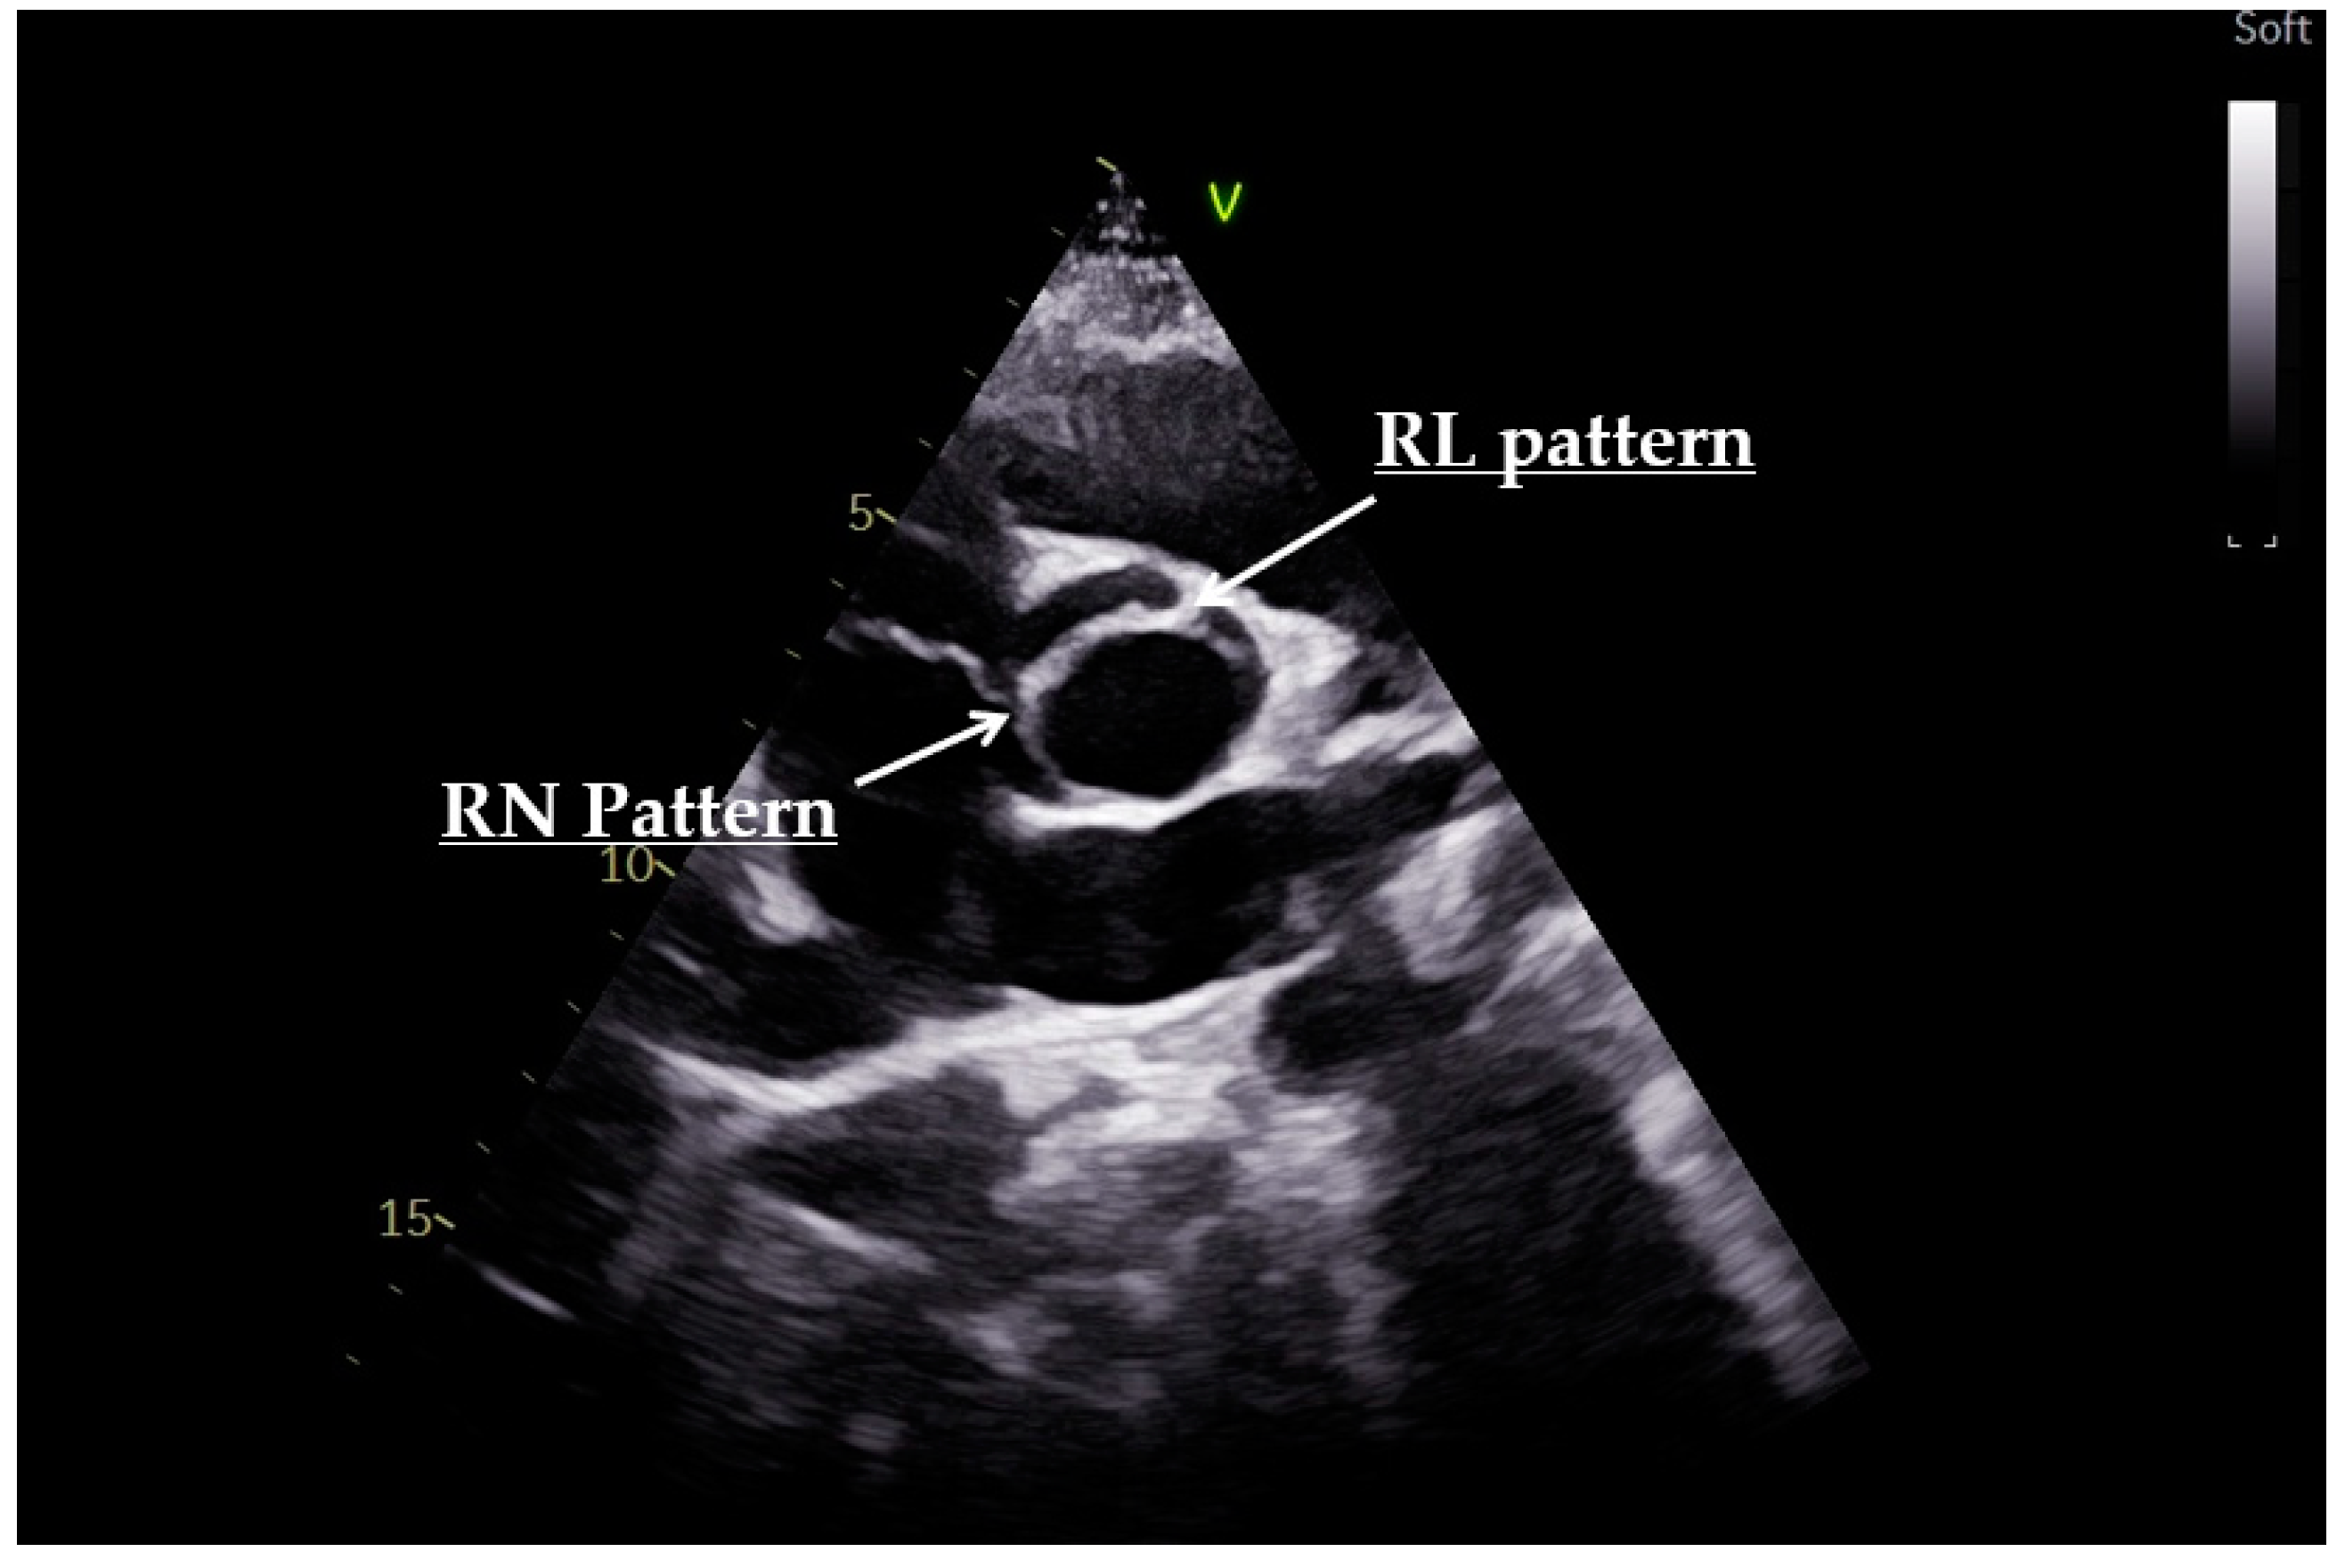

- Sievers, H.H.; Schmidtke, C. A classification system for the bicuspid aortic valve from 304 surgical specimens. J. Thorac. Cardiovasc. Surg. 2007, 133, 1226–1233. [Google Scholar] [CrossRef]